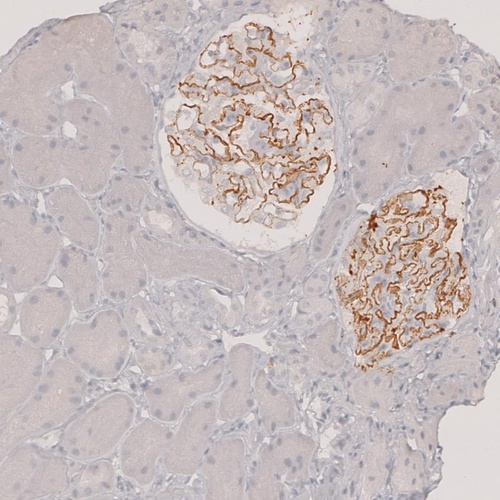

Immunohistochemistry analysis in human kidney and pancreas tissues using HPA012657 antibody. Corresponding PLA2R1 RNA-seq data are presented for the same tissues.